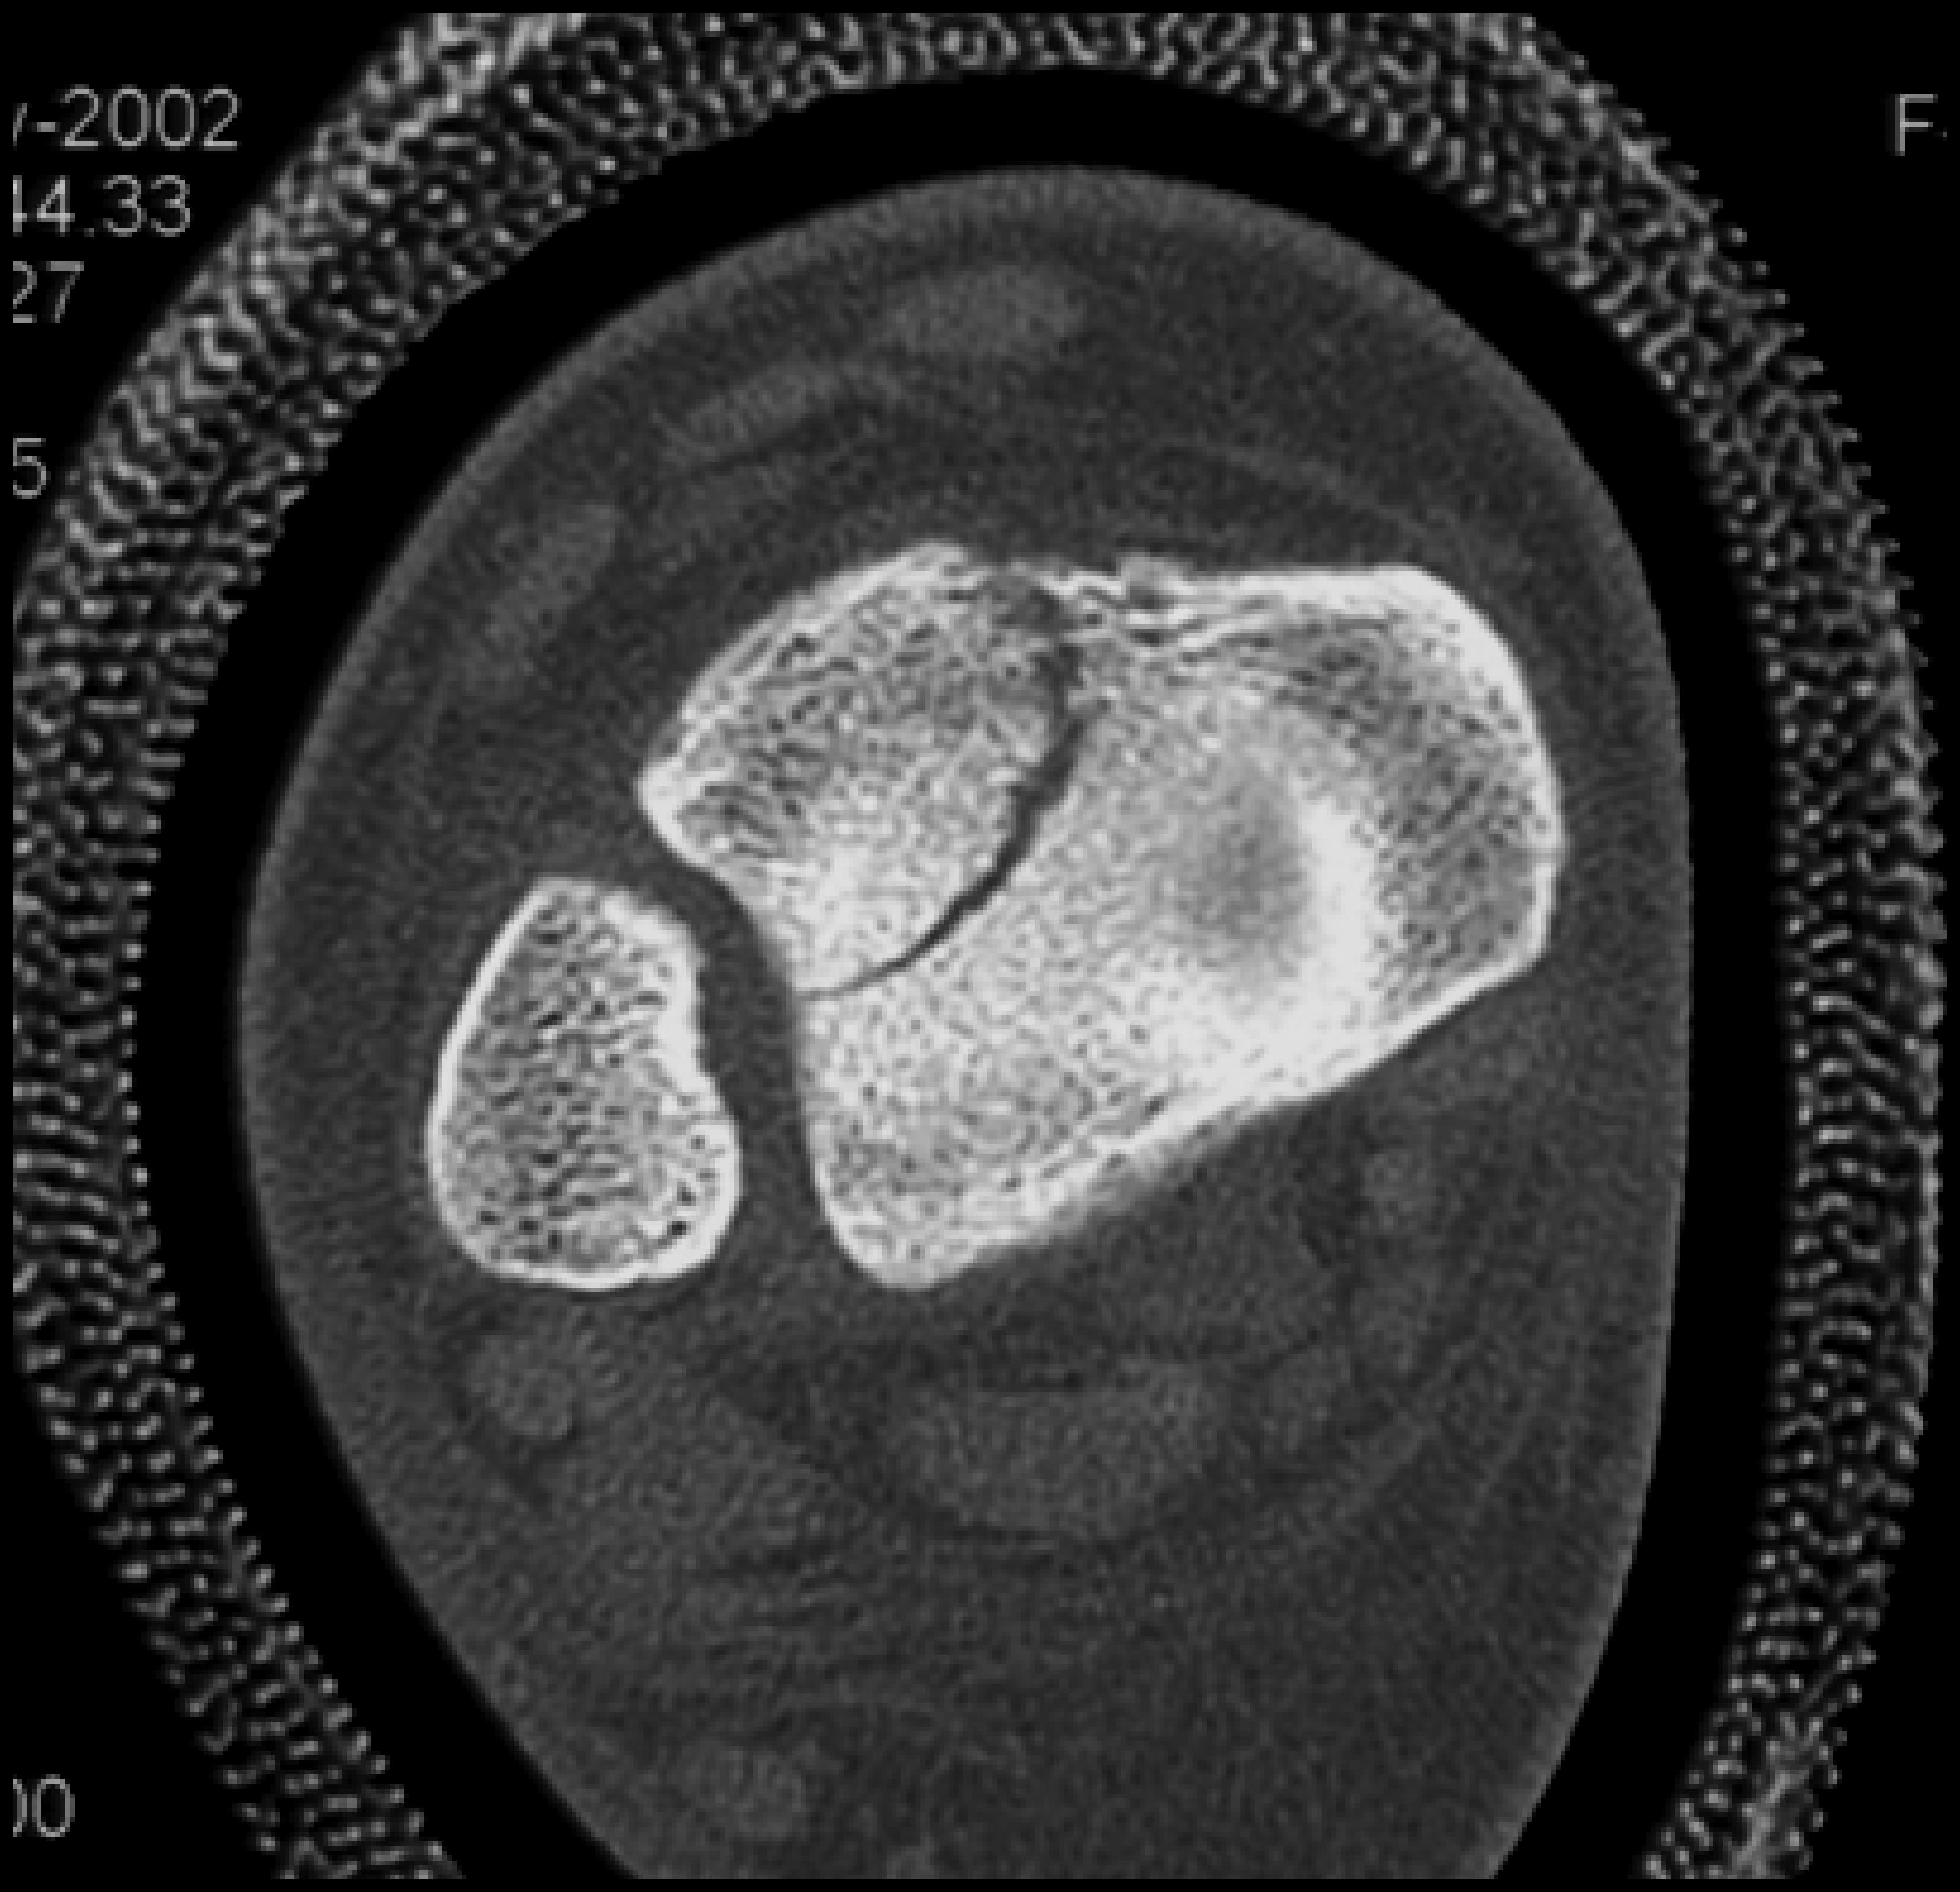

Clinical History: 12 year old female who fell down steps. She presents with left lower extremity pain.

CT Findings: Nondisplaced triplane left ankle fracture involving medial malleolus, with opened epiphysis.

Diagnosis: Minimally displaced of the medial malleolus and widening of the epiphyseal plate defined.